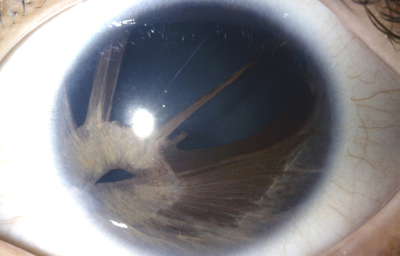

Persistencia de la membrana pupilar: Usualmente, el mecanismo de desaparición de la membrana pupilar es referido como atrofia.

La membrana pupilar es una membrana verdadera, no una malla vascular y lo que se evidencia es un cese del crecimiento de parte de la membrana, primero las arcadas vasculares centrales (6.5 meses), después el siguiente conjunto ( 7 meses al término); gradualmente la sangre deja de circular por ellas, se rompen y desaparecen sin signos de actividad inflamatoria o mecanismo clástico, mientras tanto las porciones periféricas continuan engrosando al mismo ritmo del crecimiento del Iris. El proceso es por lo tanto una cesación del crecimiento, muerte gradual e involución o reabsorción de las células comprometidas.

Es frecuente y común ver rastros o persistencia de ella en la forma de pequeños filamentos unidos al círculo menor, en ojos por lo demás normales, y la causa es un simple fallo en la completa reabsorción y atrofia de las células comprometidas.

La causa, en los casos con persistencia de una membrana extensa es mucho más difícil de explicar. No hay evidencia de herencia. Por lo tanto el error tiene que residir en alguna condición general o local, que actúe después del 5º mes de la gestación, ya que en ese momento o un poco mas tarde, casi todos los órganos están diferenciados, pero al segmento anterior del ojo le faltan los desarrollos que están en proceso; el resto del ojo generalmente es normal.

Existen múltiples variaciones en la presentación de la persistencia de la membrana pupilar, pero la mayoría se puede incluir en ciertos grupos:

Persistencia completa: especialmente aquellos casos con circulación activa son muy raros; se ha visto más la persistencia sin circulación, en la forma de una membrana blanquecina que casi flota en el acuoso o pigmentada en casos de iris oscuro.

Persistencia de la membrana pupilar, debajo tiene una pupila con normal desarrollo.

Foto propiedad desconocida

Persistencia de la membrana pupilar.

Tomada de Banigallapati et al.- Fotos tomadas de internet

Persistence incompleta: es mucho mas común y la mayoría de estos casos están dentro de los límites de la normalidad

a- Persistencia de uno o varios vasos únicos sin adherencias a la cápsula del cristalino, unidos al círculo menor y flotantes y/o unidos al circulo menor en sus dos extremos; según la pigmentación del iris pueden estar pigmentados o no desde el nacimiento. Esto es común.

b - Persistencia de vasos cápsulo-pupilares que partiendo del circulo menor, se dirigen hacia detrás del cristalino como en los casos de coloboma, pero pueden existir sin interferir en el crecimiento del Iris

c - Vasos persistentes unidos al cristalino en uno de sus extremos; parten del circulo menor y el otro extremo en contacto con el cristalino, produce una opacidad capsular anterior a veces de forma piramidal como si hubiera existido tracción sobre la cápsula.

d - Opacidades y hebras adherentes al cristalino pero no al Iris; pueden existir pequeñas opacidades diseminadas en el cristalino.

f - Opacidades en la cápsula anterior sin hebras, como huellas radiales de la membrana de aspecto grisáceo tenue, en los 360º o en un sector de la cápsula, como si la membrana hubiera hecho presión sobre la cápsula antes de atrofiarse.